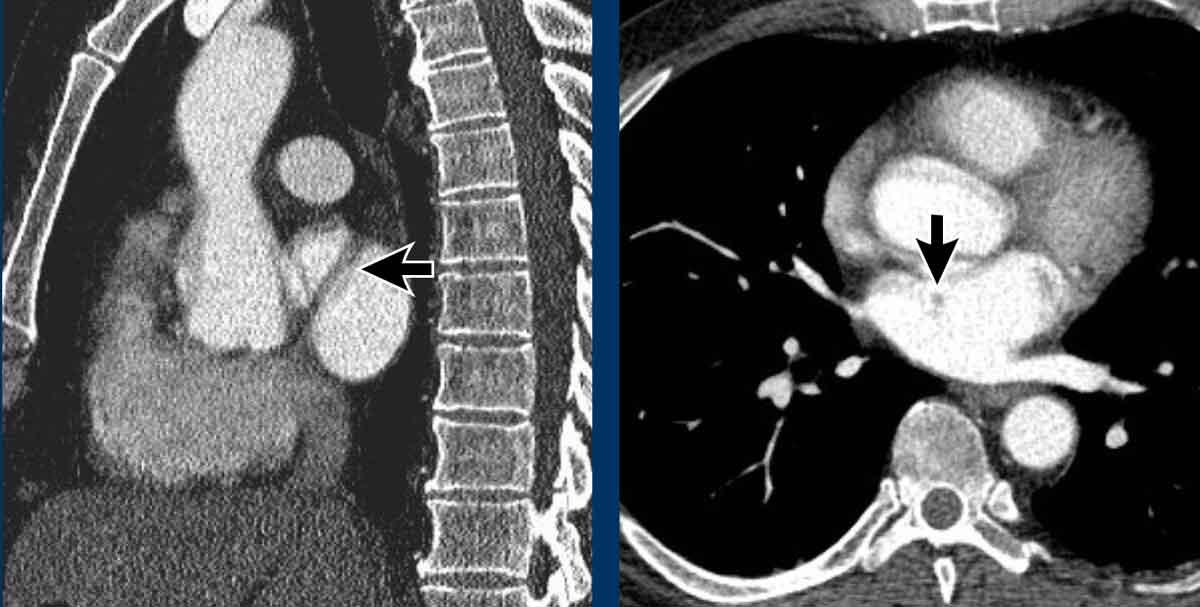

Sùi nhiễm khuẩn khổng lồ trên van ba lá ở một người dùng heroin qua đường tĩnh mạch bị viêm nội tâm mạc do S. Aureus.

Huyết khối bám thành trung tâm ở bệnh nhân bị bệnh huyết khối tắc mạch mạn tính kèm giãn buồng tim phải, phù hợp với tăng áp động mạch phổi do huyết khối tắc mạch mạn tính (CTEPH).